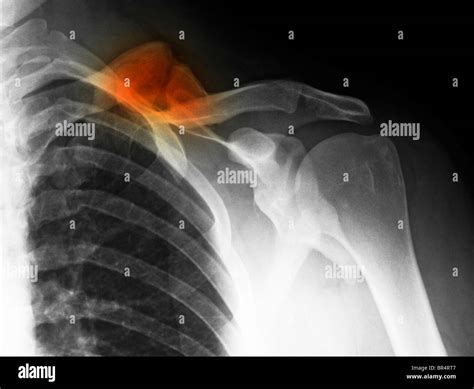

• Radiographic Evidence: An X-ray is the gold standard. A doctor looks for "bridging callus," which indicates that new bone has grown across the fracture site.

Achieving a healed broken clavicle is a milestone that signifies the end of a difficult period, but it is also a transition toward long-term maintenance. By respecting the timeline of bone regeneration and committing to the necessary physical therapy, you ensure that your shoulder remains stable and strong for years to come. Listen to your body, rely on objective diagnostic tools like X-rays to guide your progress, and do not rush the transition back to high-intensity activities. With the right care and patience, most individuals return to their full baseline of strength and daily function, putting the injury firmly in the past.